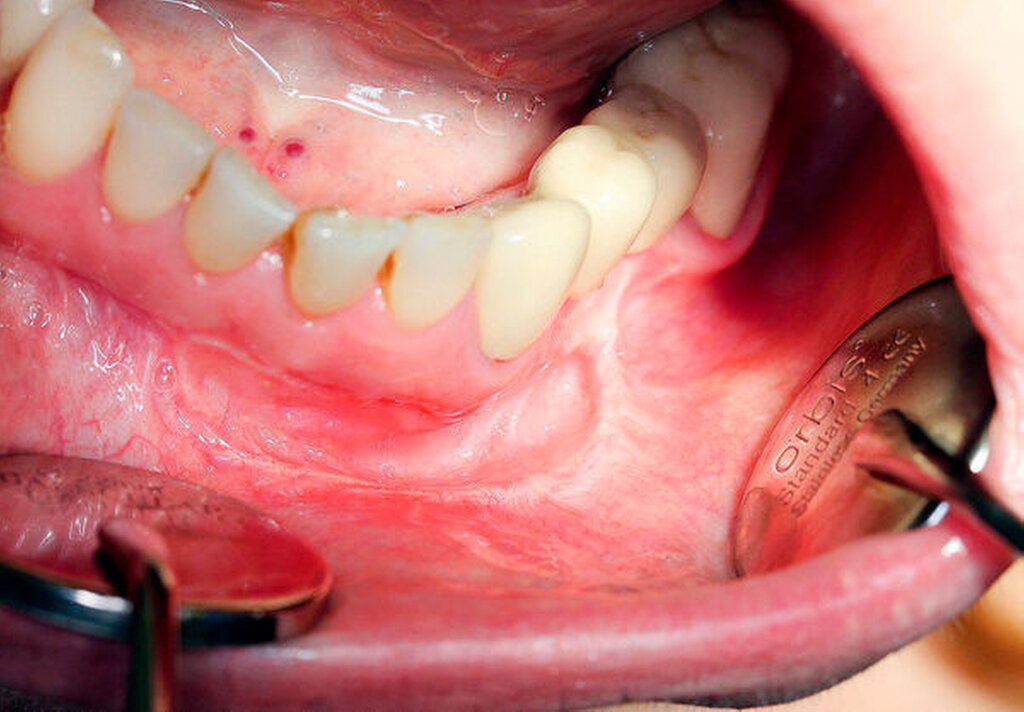

Bei der extraoralen Untersuchung konnte eine derbe Schwellung paramandibulär links palpiert werden. Diese war gering verschieblich und nicht druckdolent. Der Unterkieferrand war vollständig durchtastbar. Daneben bestand seit der Biopsie eine Hypästhesie im Bereich der Unterlippe links mit erhaltener Spitz-Stumpf-Diskrimination. Intraoral fand sich eine allseits dichte Schleimhaut. Die Raumforderung in regio 33 und 34 war palpabel und leicht verschieblich. Eine Adhärenz am Unterkiefer bestand nicht. Der Speichel war klar und exprimierbar. Eine Fluktuation oder ein Hinweis auf einen Abszess fanden sich nicht. Daneben zeigte sich ein suffizient konservativ und prothetisch versorgtes Gebiss. Die Zähne 31–33 zeigten eine positive Sensibilitätsprobe sowie eine negative Perkussionsprobe, der Zahn 37 eine negative Sensibilitäts- und Perkussionsprobe bei Zustand nach Wurzelkanalfüllung. Die Taschentiefen waren nicht erhöht.

In der durchgeführten OPG-Aufnahme zeigte sich bei mäßiger Aufnahmequalität ein konservativ, prothetisch und chirurgisch versorgtes Restgebiss (Abbildung 1) ohne Aufhellungen oder Verschattungen. Nebenbefundlich fand sich ein impaktierter und dystoper Zahn 38. In der Sonografie zeigte sich eine 13 mm × 6 mm × 7 mm große, gut abgrenzbare Raumforderung ohne dorsale Schallverstärkung. Die Patientin wurde daraufhin zur weiteren Abklärung im Intervall stationär aufgenommen.